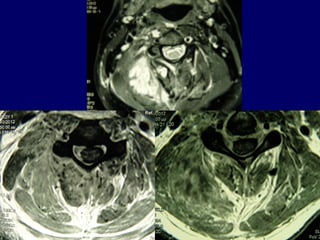

22ndnd

casecase

J. Chr.

M 69

Unknown origin

Symptoms

Neurologic deficit

Pain

Low fever

MRIMRI

TransoralTransoral

Pus evacuationPus evacuation

Follow upFollow up

Antibiotics

i-v for 2 weeks

orally for 4 months

(staphylococous aureous)

Complete neurologic recovery